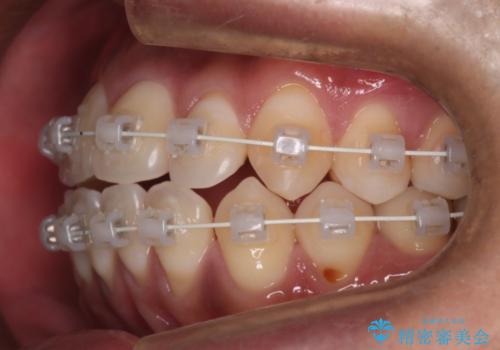

- 矯正装置

- 審美装置

- 全体的に歯並びをよくしたいとのことで来院されました。初診時、患者様はセラミック矯正とワイヤー矯正で迷われていました。

開口(オープンバイト)のため噛み合わせを考慮してワイヤー矯正を提案させていただきました。

IPR(歯と歯の間を削る処置)と顎間ゴムを行い歯並びを整える治療計画を立てました。